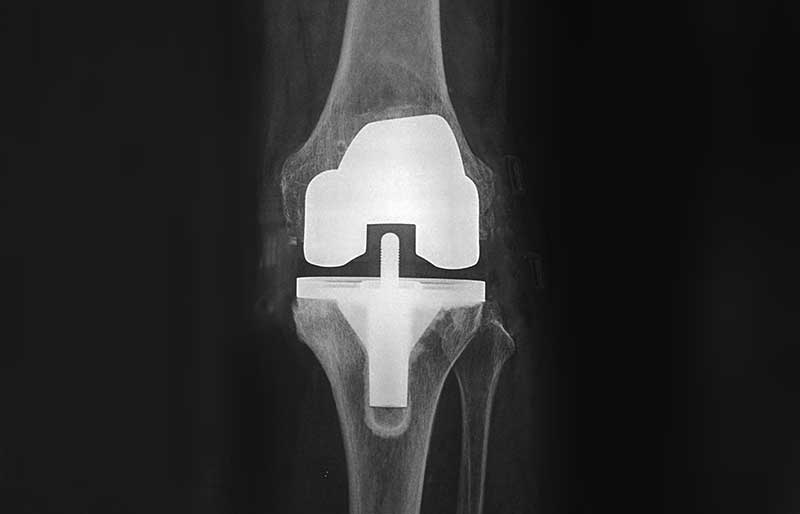

Operasi penggantian sendi lutut adalah suatu operasi untuk mengganti sendi lutut yang rusak akibat osteoartritis (penipisan tulang rawan) dengan sendi buatan yang disebut prosthesis. Penyebab utama kerusakan sendi lutut adalah osteoartritis (baca pen- jelasan tentang “Osteoartritis”) dan sendi yang paling sering terserang osteoartritis adalah lutut.

Operasi penggantian sendi lutut merupakan pengobatan terbaik untuk osteoartritis lutut stadium 3 dan 4. Ada empat tujuan operasi ini, yaitu menghilangkan rasa sakit sendi yang telah rusak, memperbaiki lingkup gerak sendi yang sebelumnya kaku dan terbatas, mengembalikan kemampuan penderita melakukan aktivitas harian tanpa rasa sakit, dan meningkatkan kualitas hidup sehingga penderita kerusakkan sendi dapat menjalani hidup secara aktif bebas dari nyeri sendi.